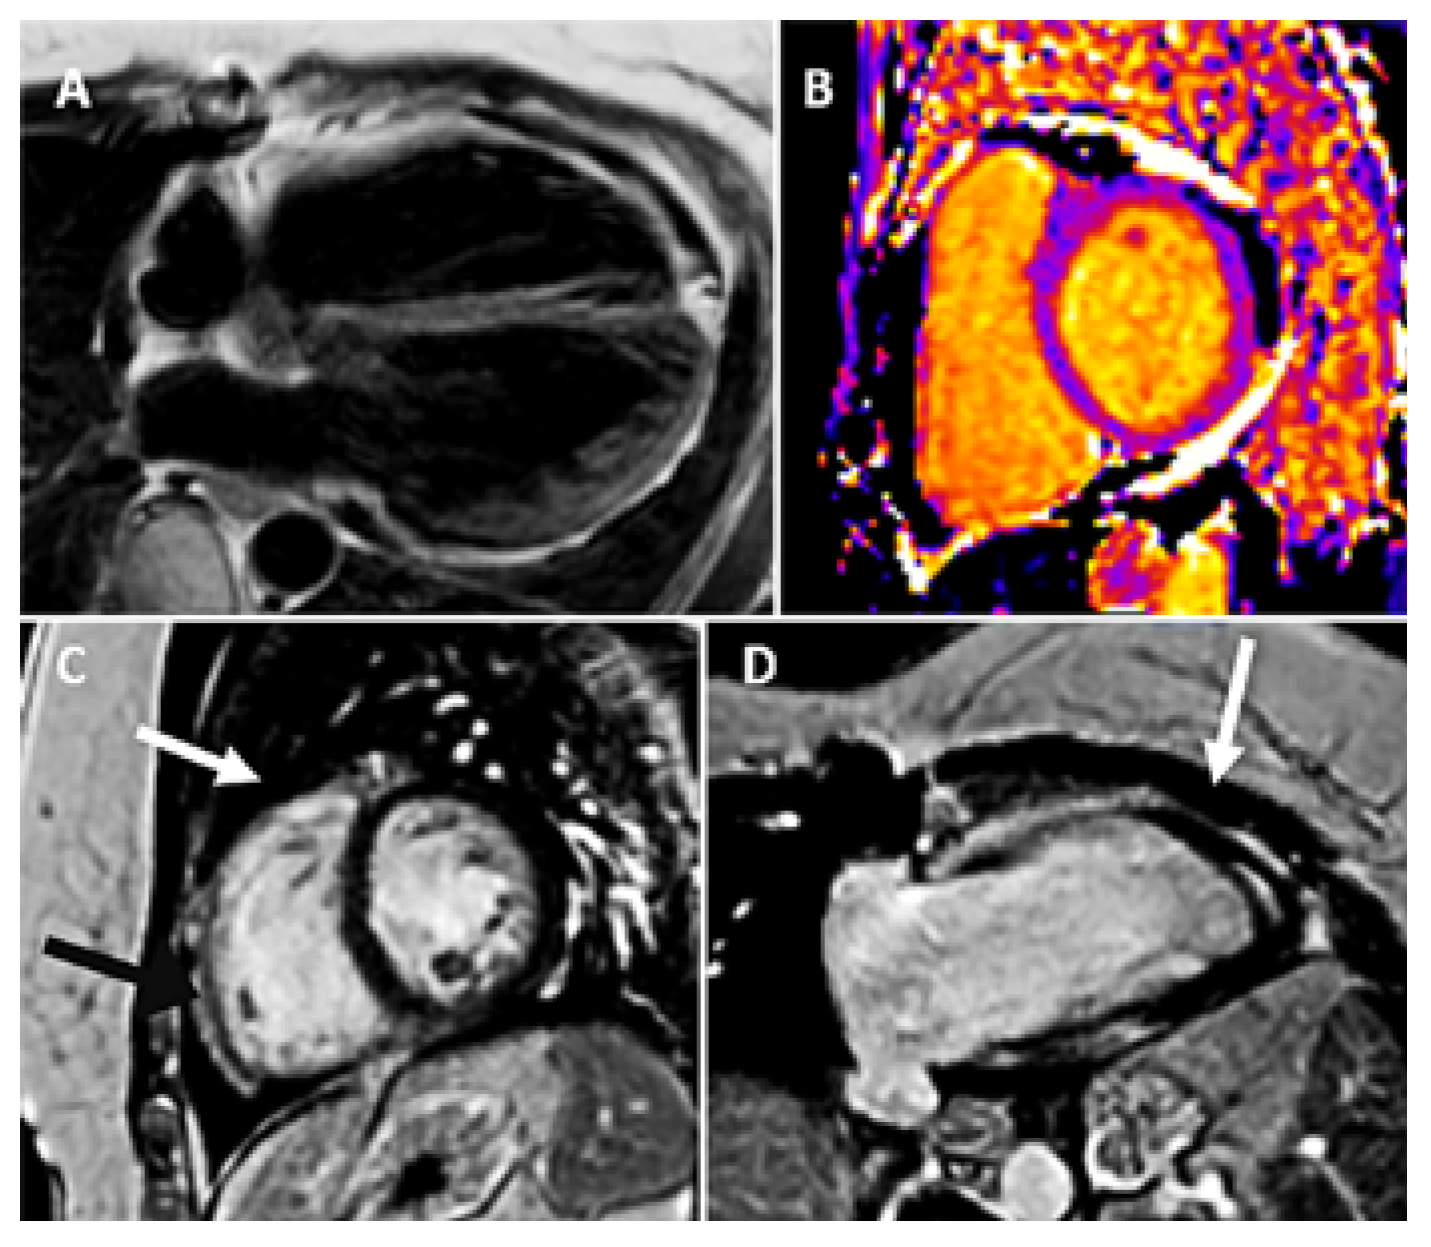

Intrapericardial Doppler Flow Signals in a Patient with Pericardial Effusion

Case Description

Discussion